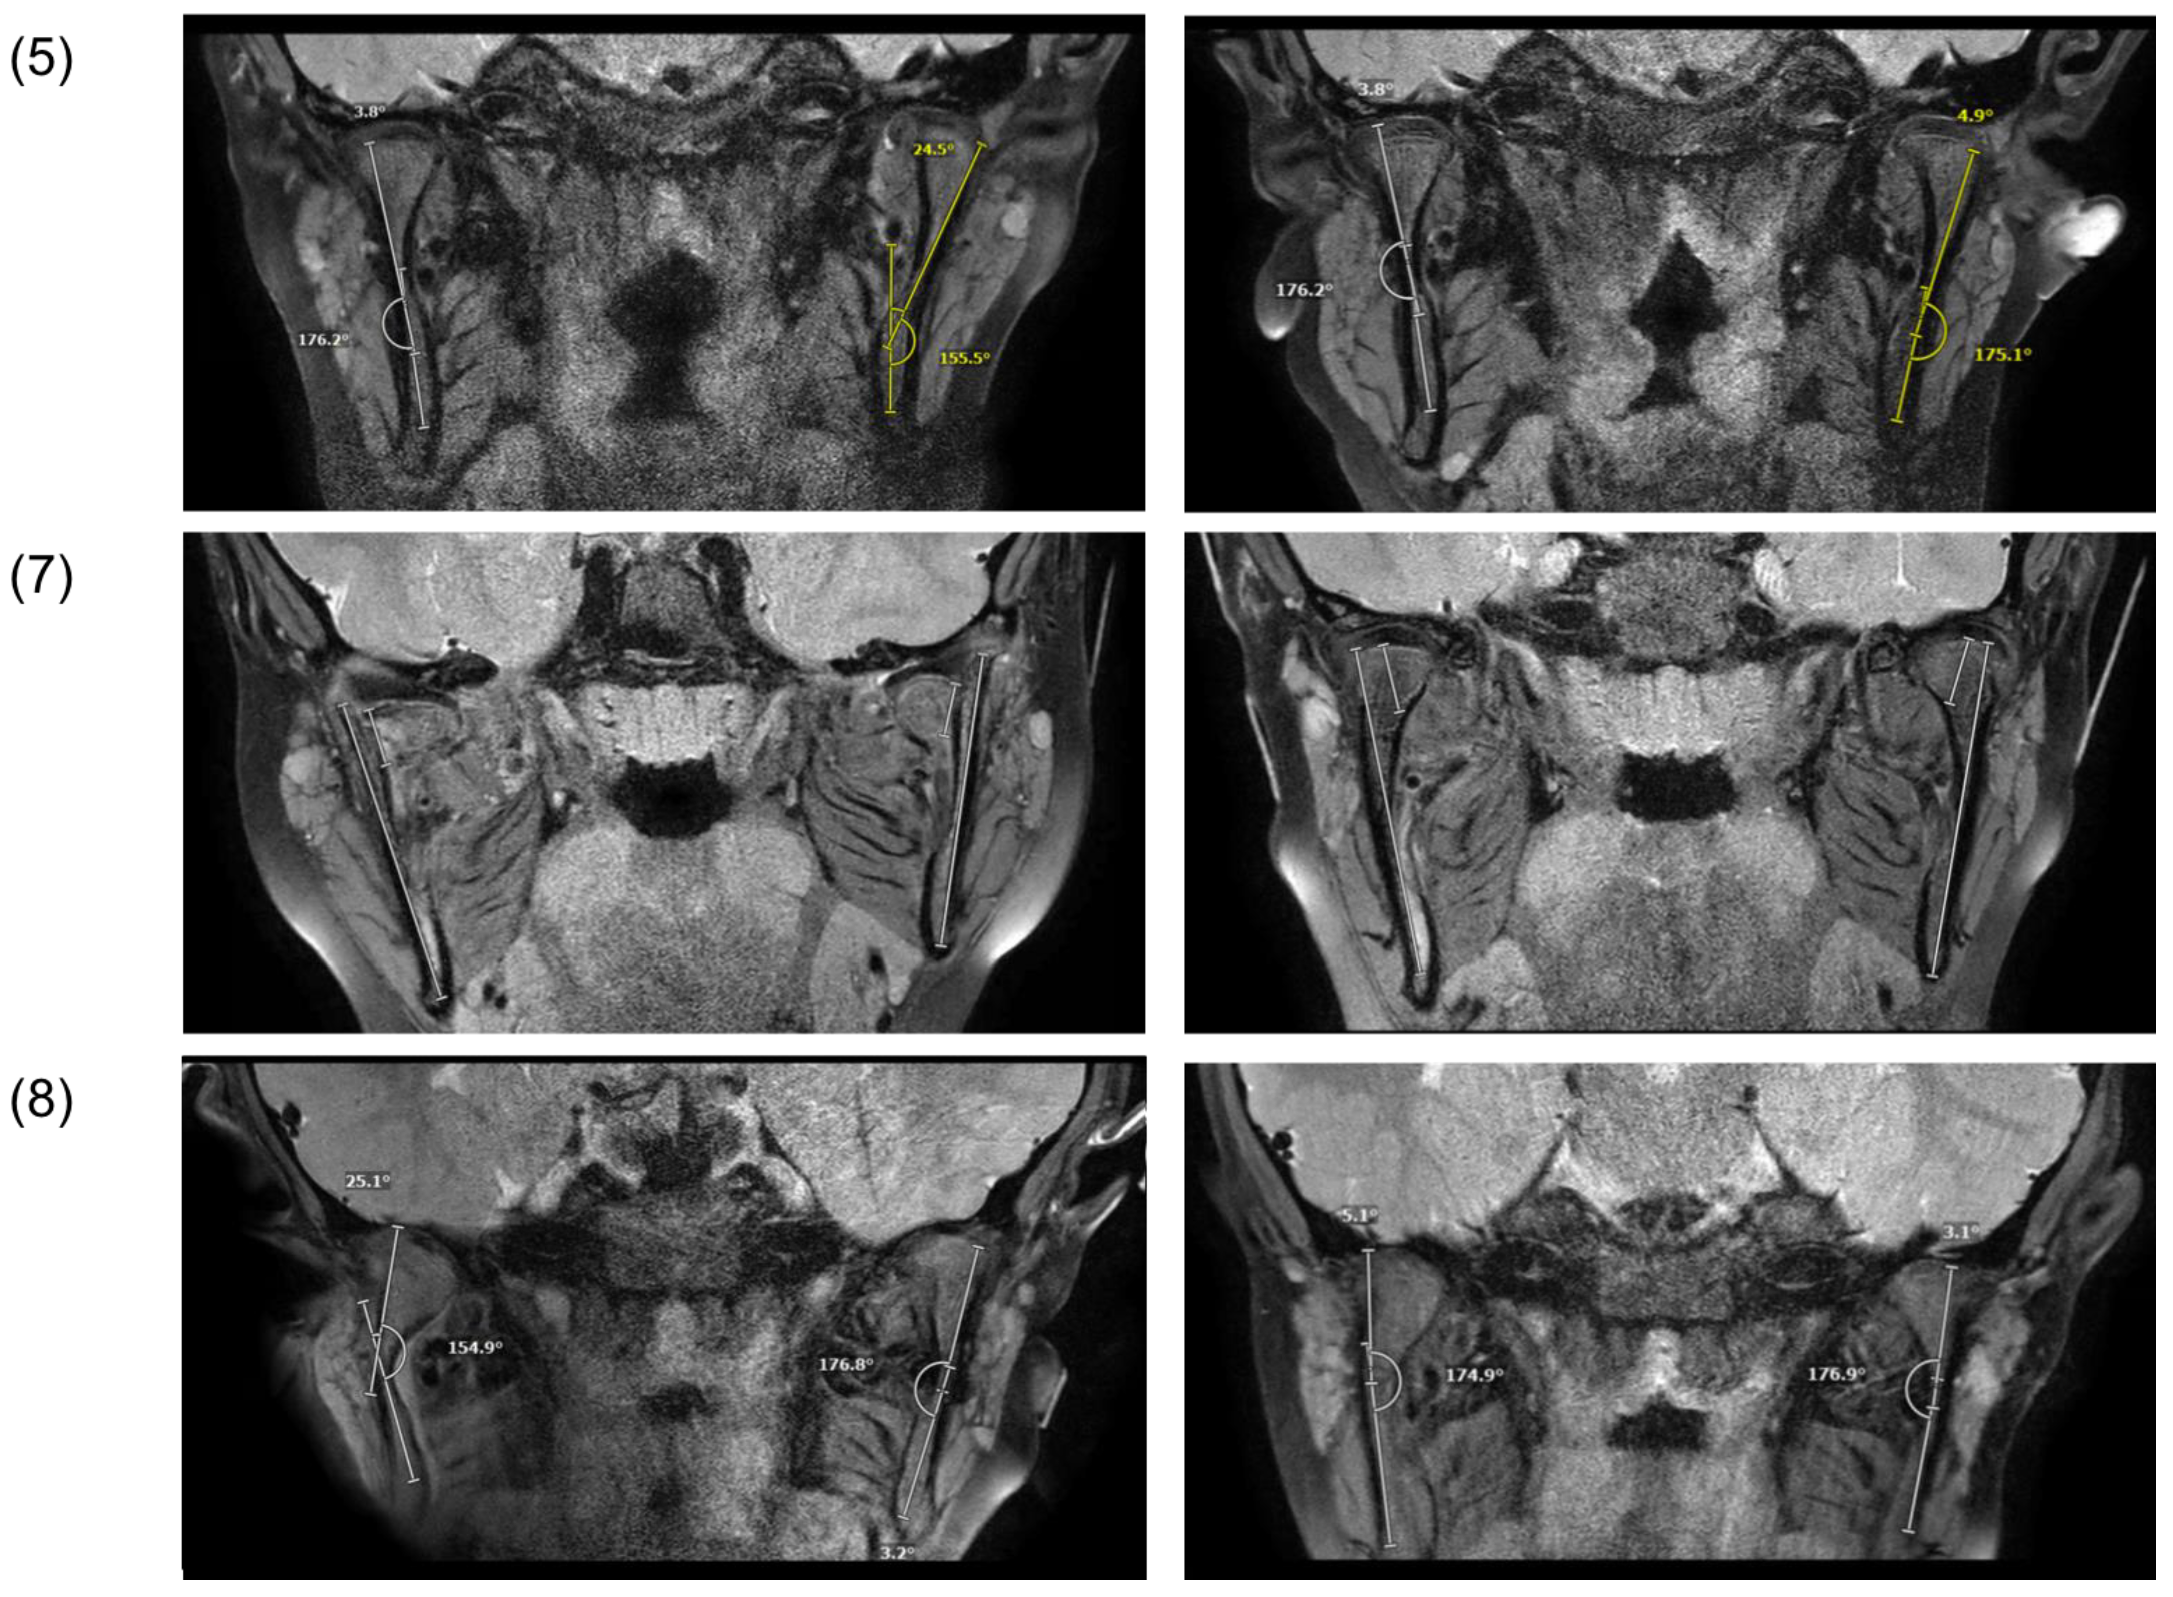

3.3. Radiological Findings